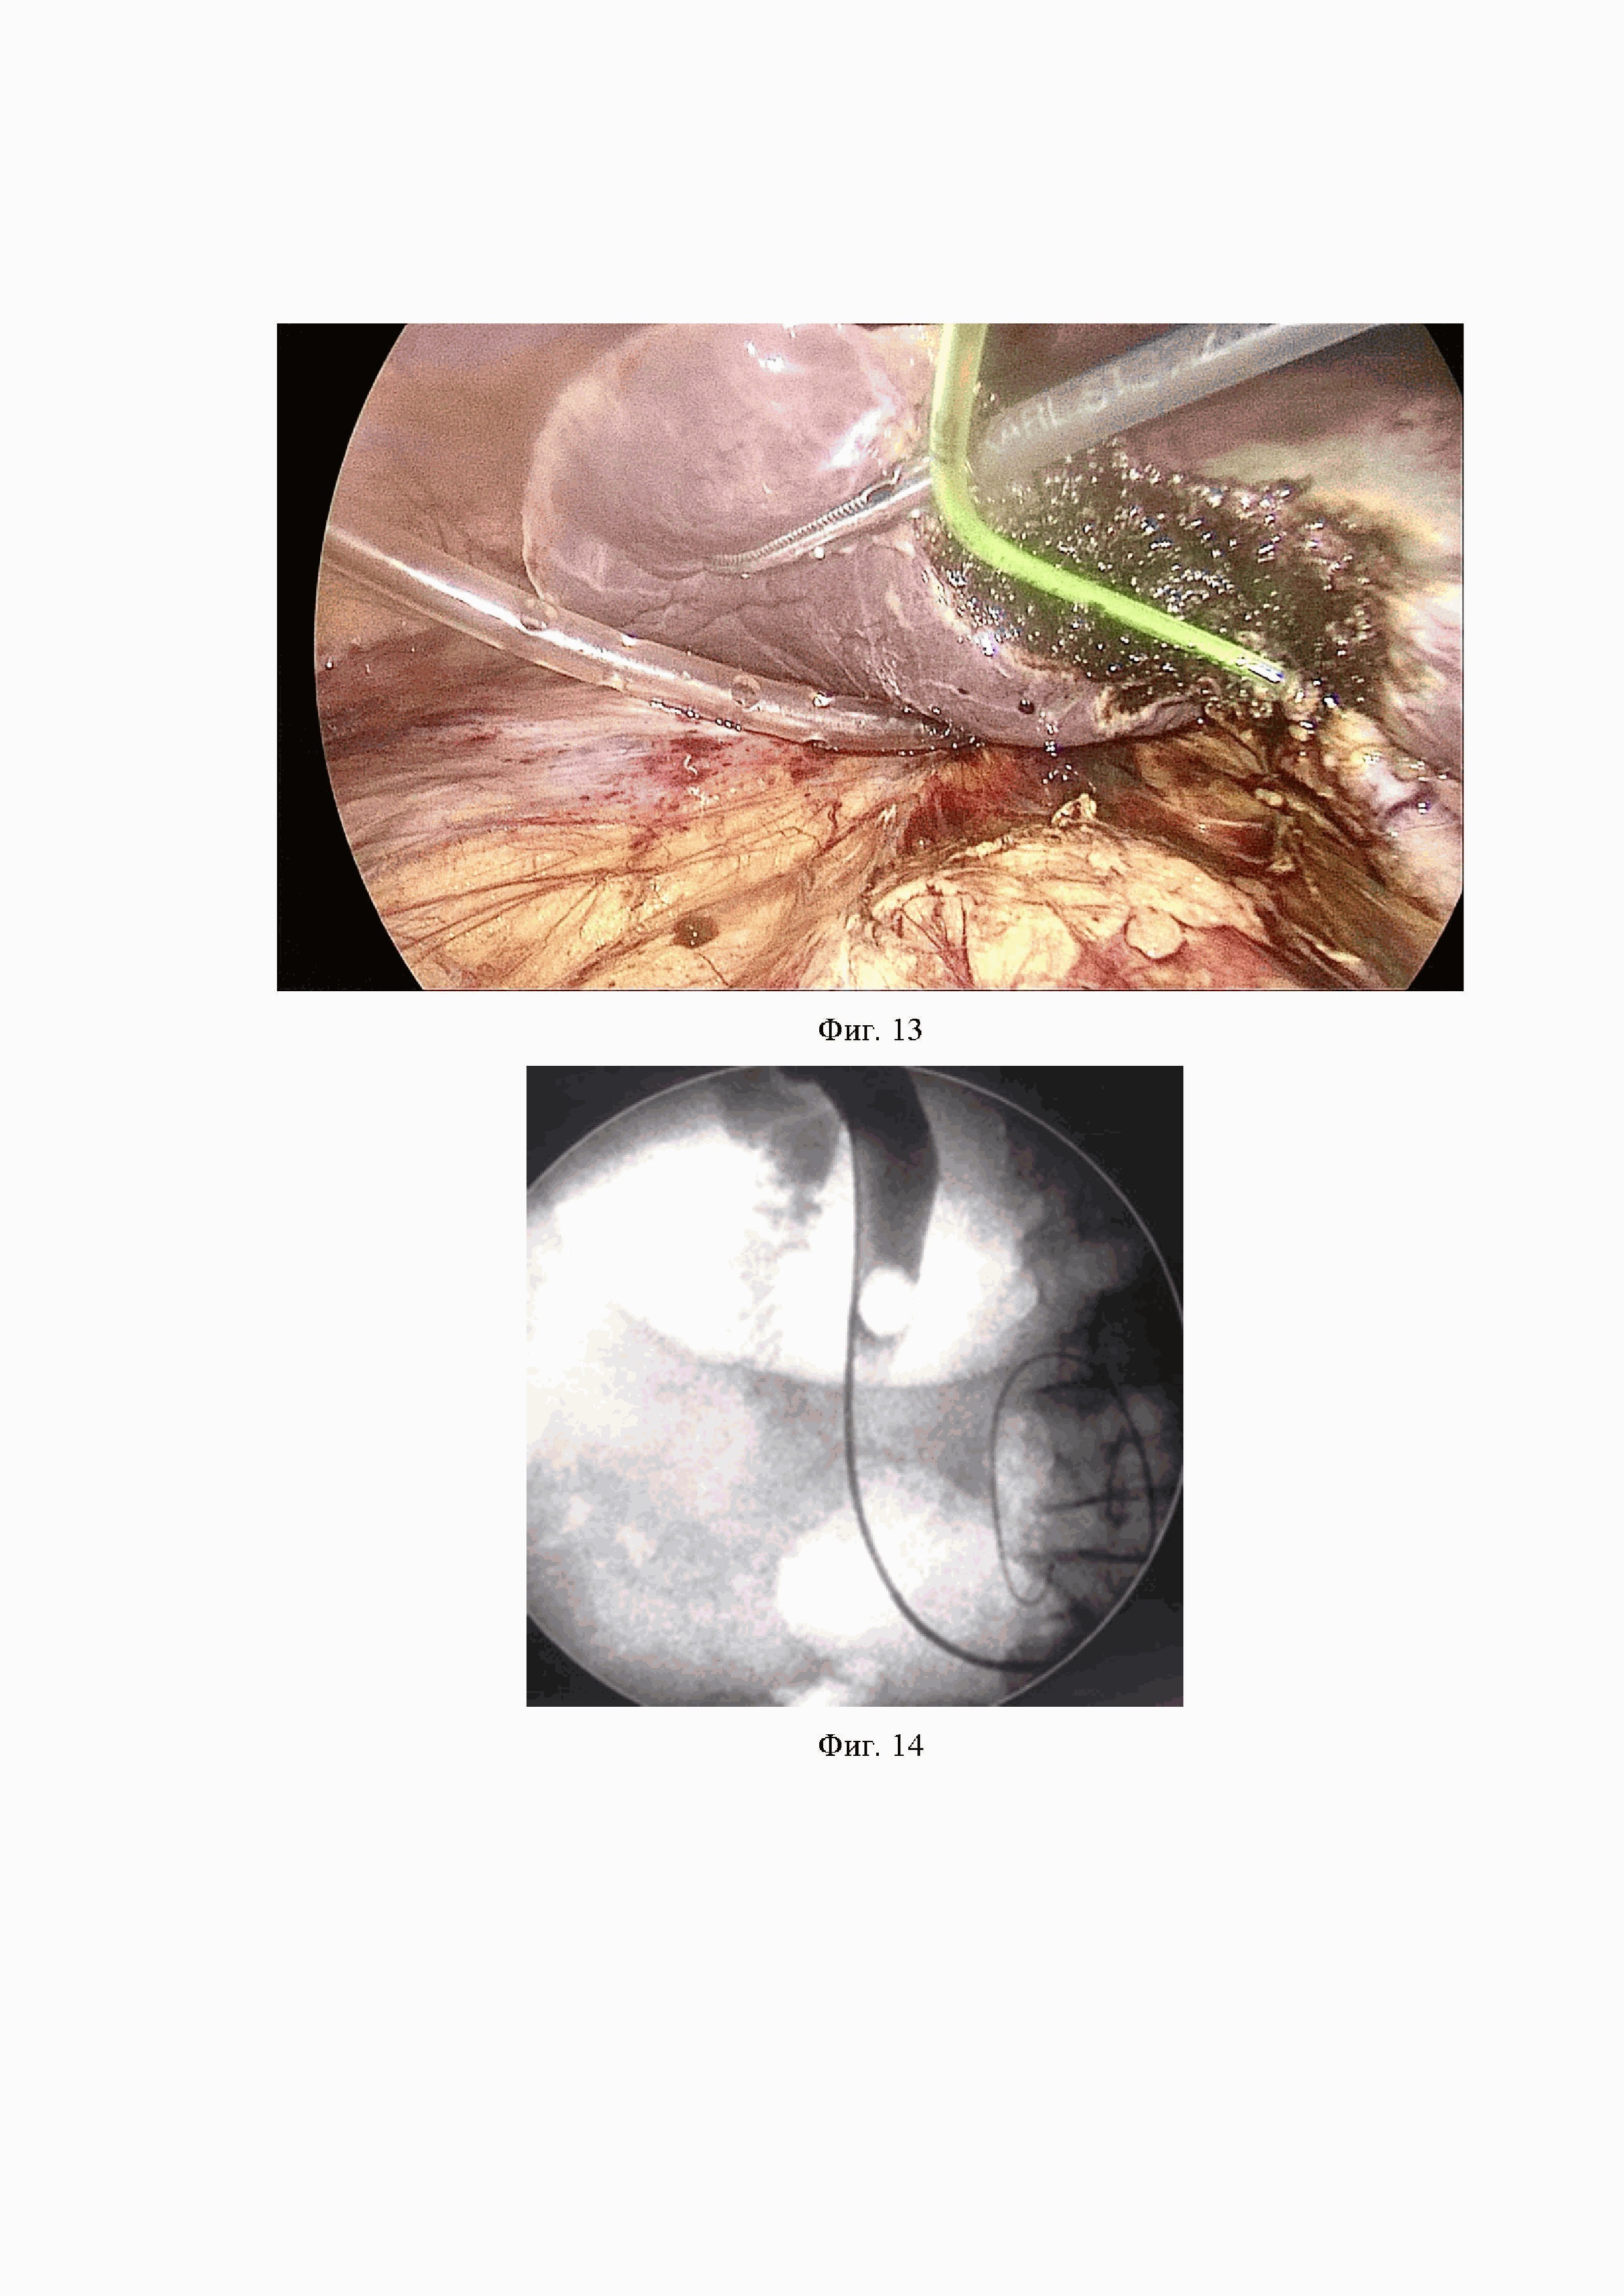

По низведенному в просвет ДПК тефлоновому проводнику выполнена канюляция БДС (Фиг. 15), произведена РХПГ, в просвете ОЖП визуализированы единичные дефекты наполнения, выполнена ПСТ, корзинкой Дормиа в просвет ДПК извлечены три конкремента коричневого цвета от 5 до 11 мм со сладжем. При контрольной рентгеноскопии дефектов наполнения не обнаружено.

На Фиг. 14 - 16 продемонстрированы холангиограммы этапов хирургического лечения пациентки с ЖКБ, хроническим калькулезным холециститом, осложненным холедохолитиазом и механической желтухой. Фиг. 14 - низведение тефлонового проводника через зону БДС в просвет ДПК. Фиг. 15 - этап эндоскопической канюляции БДС и заведения гидрофильного проводника в желчные протоки (черная стрелка указывает на тефлоновый проводник, установленный антеградно, белая – на гидрофильный проводник, установленный ретроградно). Фиг. 16. - послеоперационный период, дефектов наполнения не определяется.